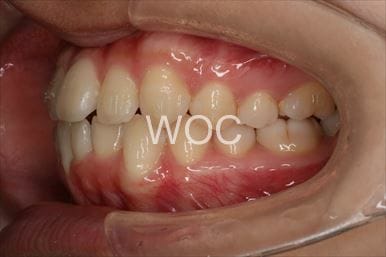

治療前3

治療後3